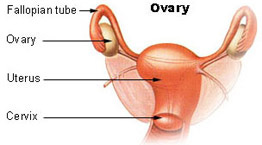

Anatomy and Histology of Ovary and Fallopian Tubes

Ovaries are essential to the fertility and cycling of reproductive activity in women and girls by controlling the development of the dominant follicle (which contains the developing ovum or egg) and producing estrogen and progesterone hormones.

The fallopian tubes are hollow, tubular structures, bilateral, 8 - 12 cm long and 0.5 - 1.2 cm in diameter that extend from the posterior of the uterus laterally towards the ovaries.

Most ovarian cancers are epithelial, but most testicular tumors derive from germ cells or sex cord stroma. Many ovarian cancers arise, in fact, from the fallopian tubes or the uterus, not from the ovaries themselves, as will be discussed in a future essay.